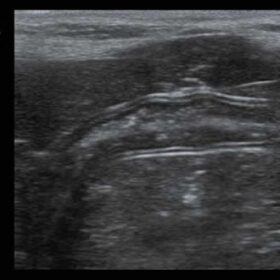

Ultrasound Mindray Z60 – Image Gallery

- PSHI (Phase Shift Harmonic Imaging) Purified Harmonic Imaging for better contrast resolution providing clearer images with excellent resolution and less noise.

- iBeam, Permits use of multiple scanned angles to form a single image, resulting in enhanced contrast resolution and improved visualization

- iClear, Gain improved image quality based on auto structure detection